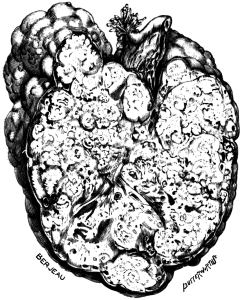

| 1. | Secondary Cancer of the Ovary | 15 |

| 2. | Secondary Cancer of the Ovary in Section | 15 |